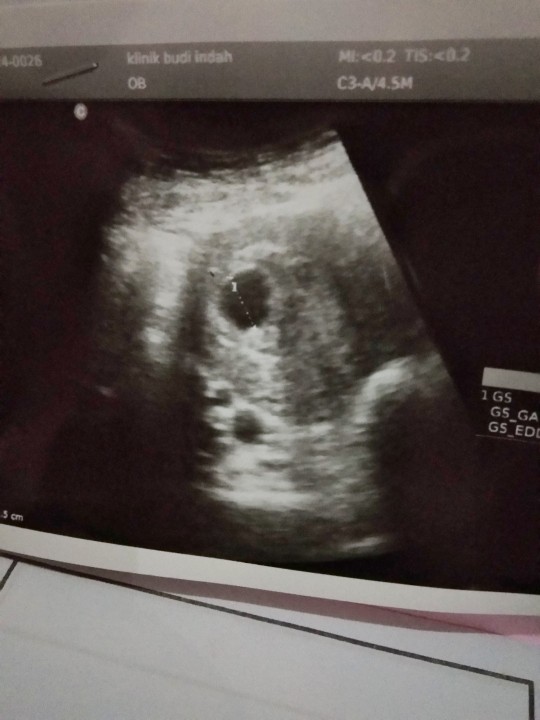

usg

Bun,usia 6w gambar usg nya kygini normal ga sih Bun?? Tadi dokternya bilang, ga berkembang masa?? Disuruh balik lagi seminggu selanjutnya untuk di usg lagi

Masih terlalu kecil , blum terlihat memang klo usia segitu ,, Betul , nanti balik lg stelah bbrpa minggu,,

Baca lagiAku semalem usg 6w2d juga baru kantongnya bun, dan dokter bilang itu wajar. Suruh balik usg sebulan lagi.

ini punya saya bund uk 6w....skrg udah 17w5d.....positif thinking dl bund, cb usg lagi 2minggu lagi....